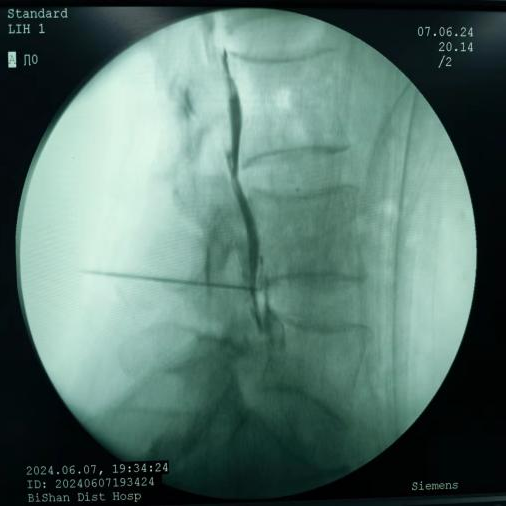

鞘內(nèi)泵植入術(shù):將藥物輸注導(dǎo)管植入鞘內(nèi),通過體外或體內(nèi)泵持續(xù)輸入鎮(zhèn)痛藥物,作用于中樞阿片受體,治療癌痛及頑固性疼痛。

鞘內(nèi)泵植入術(shù)